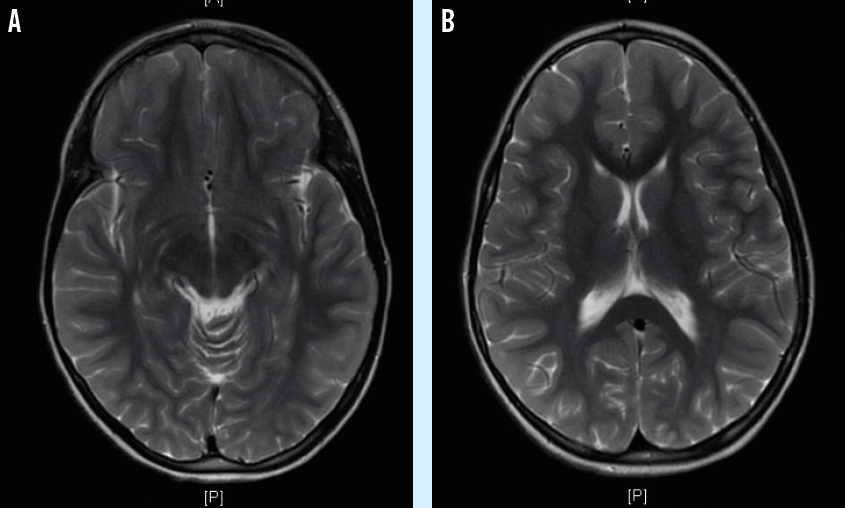

The girl was admitted to the pediatric intensive care unit and was started on a regimen of broad-spectrum intravenous antibiotics and acyclovir. She later developed visual hallucinations. Magnetic resonance imaging (MRI) of the brain (A and B) showed diffuse, abnormal leptomeningeal enhancement suggesting meningitis or encephalitis. No intracranial masses were noted on MRI. Electroencephalography results showed signs of encephalitis.